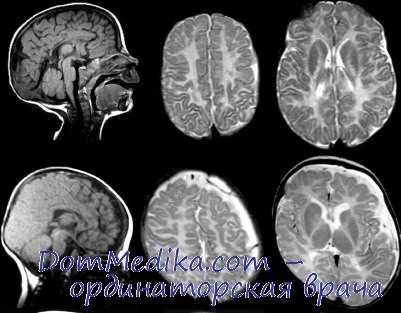

ж. Окончательный диагноз может быть установлен только на аутопсии. Врожденный стридор и нистагм у мальчиков должны настораживать врачей в отношении возможного наличия данного заболевания. Инструментальные методы не могут отличить данное заболевание от других форм поражения белого вещества. На КТ выявляется значительное снижение плотности белого вещества и его прогрессирующая атрофия. МРТ обнаруживает нарушение миединизации; мозг постоянно напоминает мозг новорожденного.

Диагноз может быть заподозрен на основании тщательной клинической оценки, подробной истории болезни пациента и различных специализированных обследований, таких как магнитно-резонансная томография (МРТ). Распознавание ранних дефектов миелинизации, таких как отсутствие миелинизации в мозжечке и стволе мозга, может помочь в ранней диагностике тяжелых форм синдрома. Доступно молекулярно-генетическое тестирование на ген PLP1 для подтверждения диагноза. Разработана и пренатальная диагностика и преимплантационная генетическая диагностика.

С целью диагностики вида метаболической аномалии проводится целый ряд биохимических тестов с определением уровня ферментов и накапливающихся метаболитов. Очаги демиелинизации хорошо визуализируются при помощи МРТ, могут быть обнаружены и на КТ головного мозга. Обычно демиелинизация видна на МРТ головного мозга еще до клинической манифестации лейкодистрофии. Благодаря развитию генетики, лейкодистрофия имеет разработанную ДНК-диагностику, а отдельные ее формы (метахроматическая, адренолейкодистрофия, глобоидно-клеточная) — возможность пренатального диагностирования.